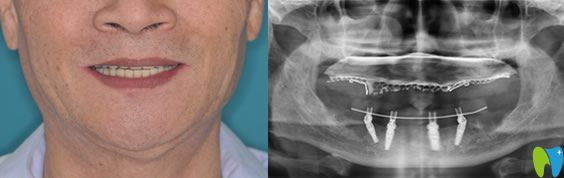

口腔情況:全口牙缺失;

種植方案:佛山智媄口腔醫(yī)生對(duì)林大爺?shù)目谇缓脱啦酃乔闆r進(jìn)行了自信的分析,建議采用all-on-4全口種植技術(shù)。

All-on-4種植技術(shù):是歐美全新的種植牙技術(shù),也是非常適合半口及全口牙缺失的修復(fù)方法。僅需植入4顆人工牙根,就能將半口牙固定,一次完成,痛苦小,而且種植后的牙齒當(dāng)天就可以吃東西,能真正的做到即種即用。

林大爺做種植牙后感言:一直覺得像自己的情況需要種10幾顆牙呢,沒(méi)想到僅僅種了4顆種植體就“長(zhǎng)出”了一排牙齒。而且在整個(gè)種植過(guò)程中沒(méi)有感覺到疼痛,醫(yī)生手法很輕,術(shù)后出血也很少,真的很意外我這么大年紀(jì)的人了,也恢復(fù)的很快,現(xiàn)在的牙齒可好用了,像年輕時(shí)的真牙一樣,終于能吃肉了!